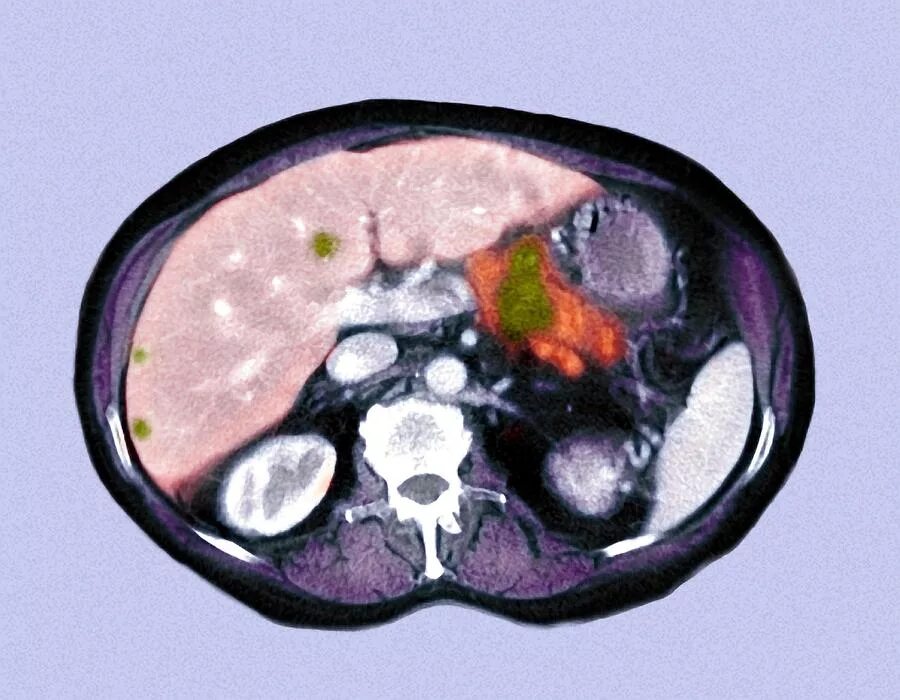

Метастазы в поджелудочную железу прогноз